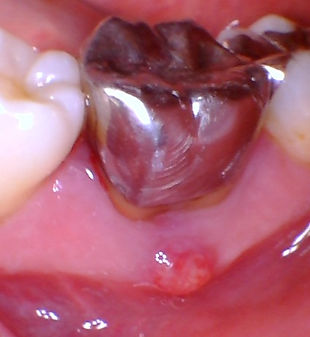

broken silver filling